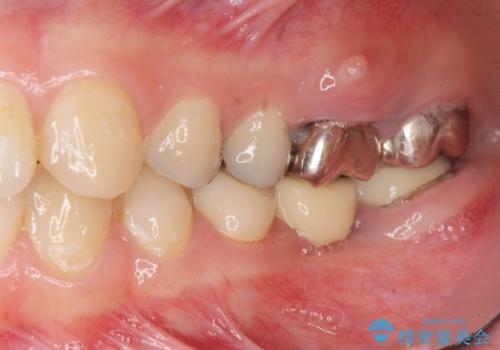

奥歯を2本失ったのち、しっかりと噛める環境へと整備するため、しっかりと骨の造成を行い清掃性を高めたインプラント治療を行っていくこととしました。

インプラントの仕上がりを見越して、ただ埋入するだけではなく長期的な予後を見込むには清掃のしやすい環境を整備することが大切です。

今回は大きく吸収してしまった歯槽骨をしっかりと造成することで、歯間ブラシを行いやすいインプラント周囲環境を整備することができました。